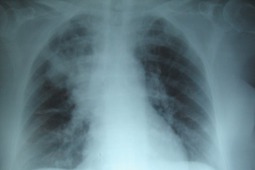

Przewlekłe infekcje dolnych dróg oddechowych spowodowane przez Pseudomonas aeruginosa są częstymi...

Leczenie skojarzone iwakaftorem i lumakaftorem prowadzi do wzrostu wartości wskaźnika FEV1 u...